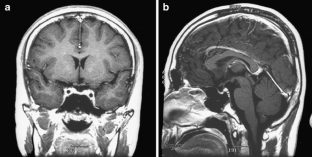

This case involves an 18-year-old man who presented with abnormal behavior, impairment in recent memory, and emotional change. Five years ago, he received five cycles of chemotherapy using cisplatin and ectoposide and 24G of local radiotherapy for clinical diagnosis of suprasellar germinoma in another hospital. The tumor was then completely resolute. Magnetic resonance imaging in our hospital revealed a large fatty mass located primarily in the septum pellucidum and some portions of the corpus callosum; a heterogeneous enhancing tumor was observed in the surrounding area. The second tumor was completely removed. The histological diagnosis was mixed GCTs containing the component of a germinoma and a mature teratoma.

Fig. 3